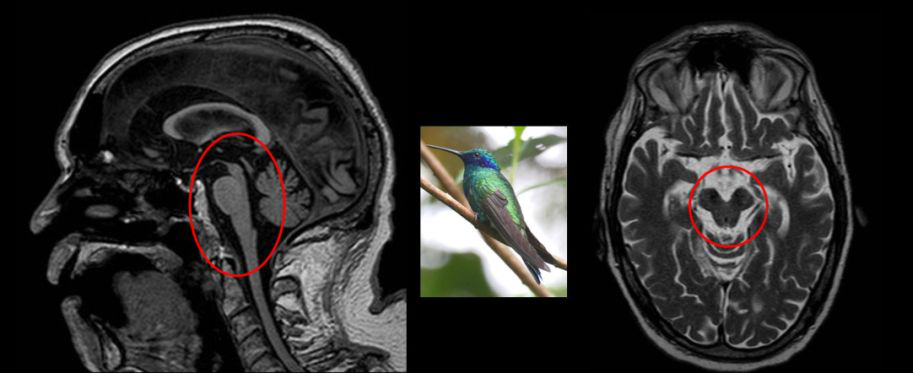

PSP 的 MR 常出現(xiàn):特征是中腦和被蓋萎縮;在矢狀位中,中腦被蓋萎縮形似「蜂鳥」;在軸位中,中腦萎縮,頂蓋和大腦腳保留形似「米老鼠」。